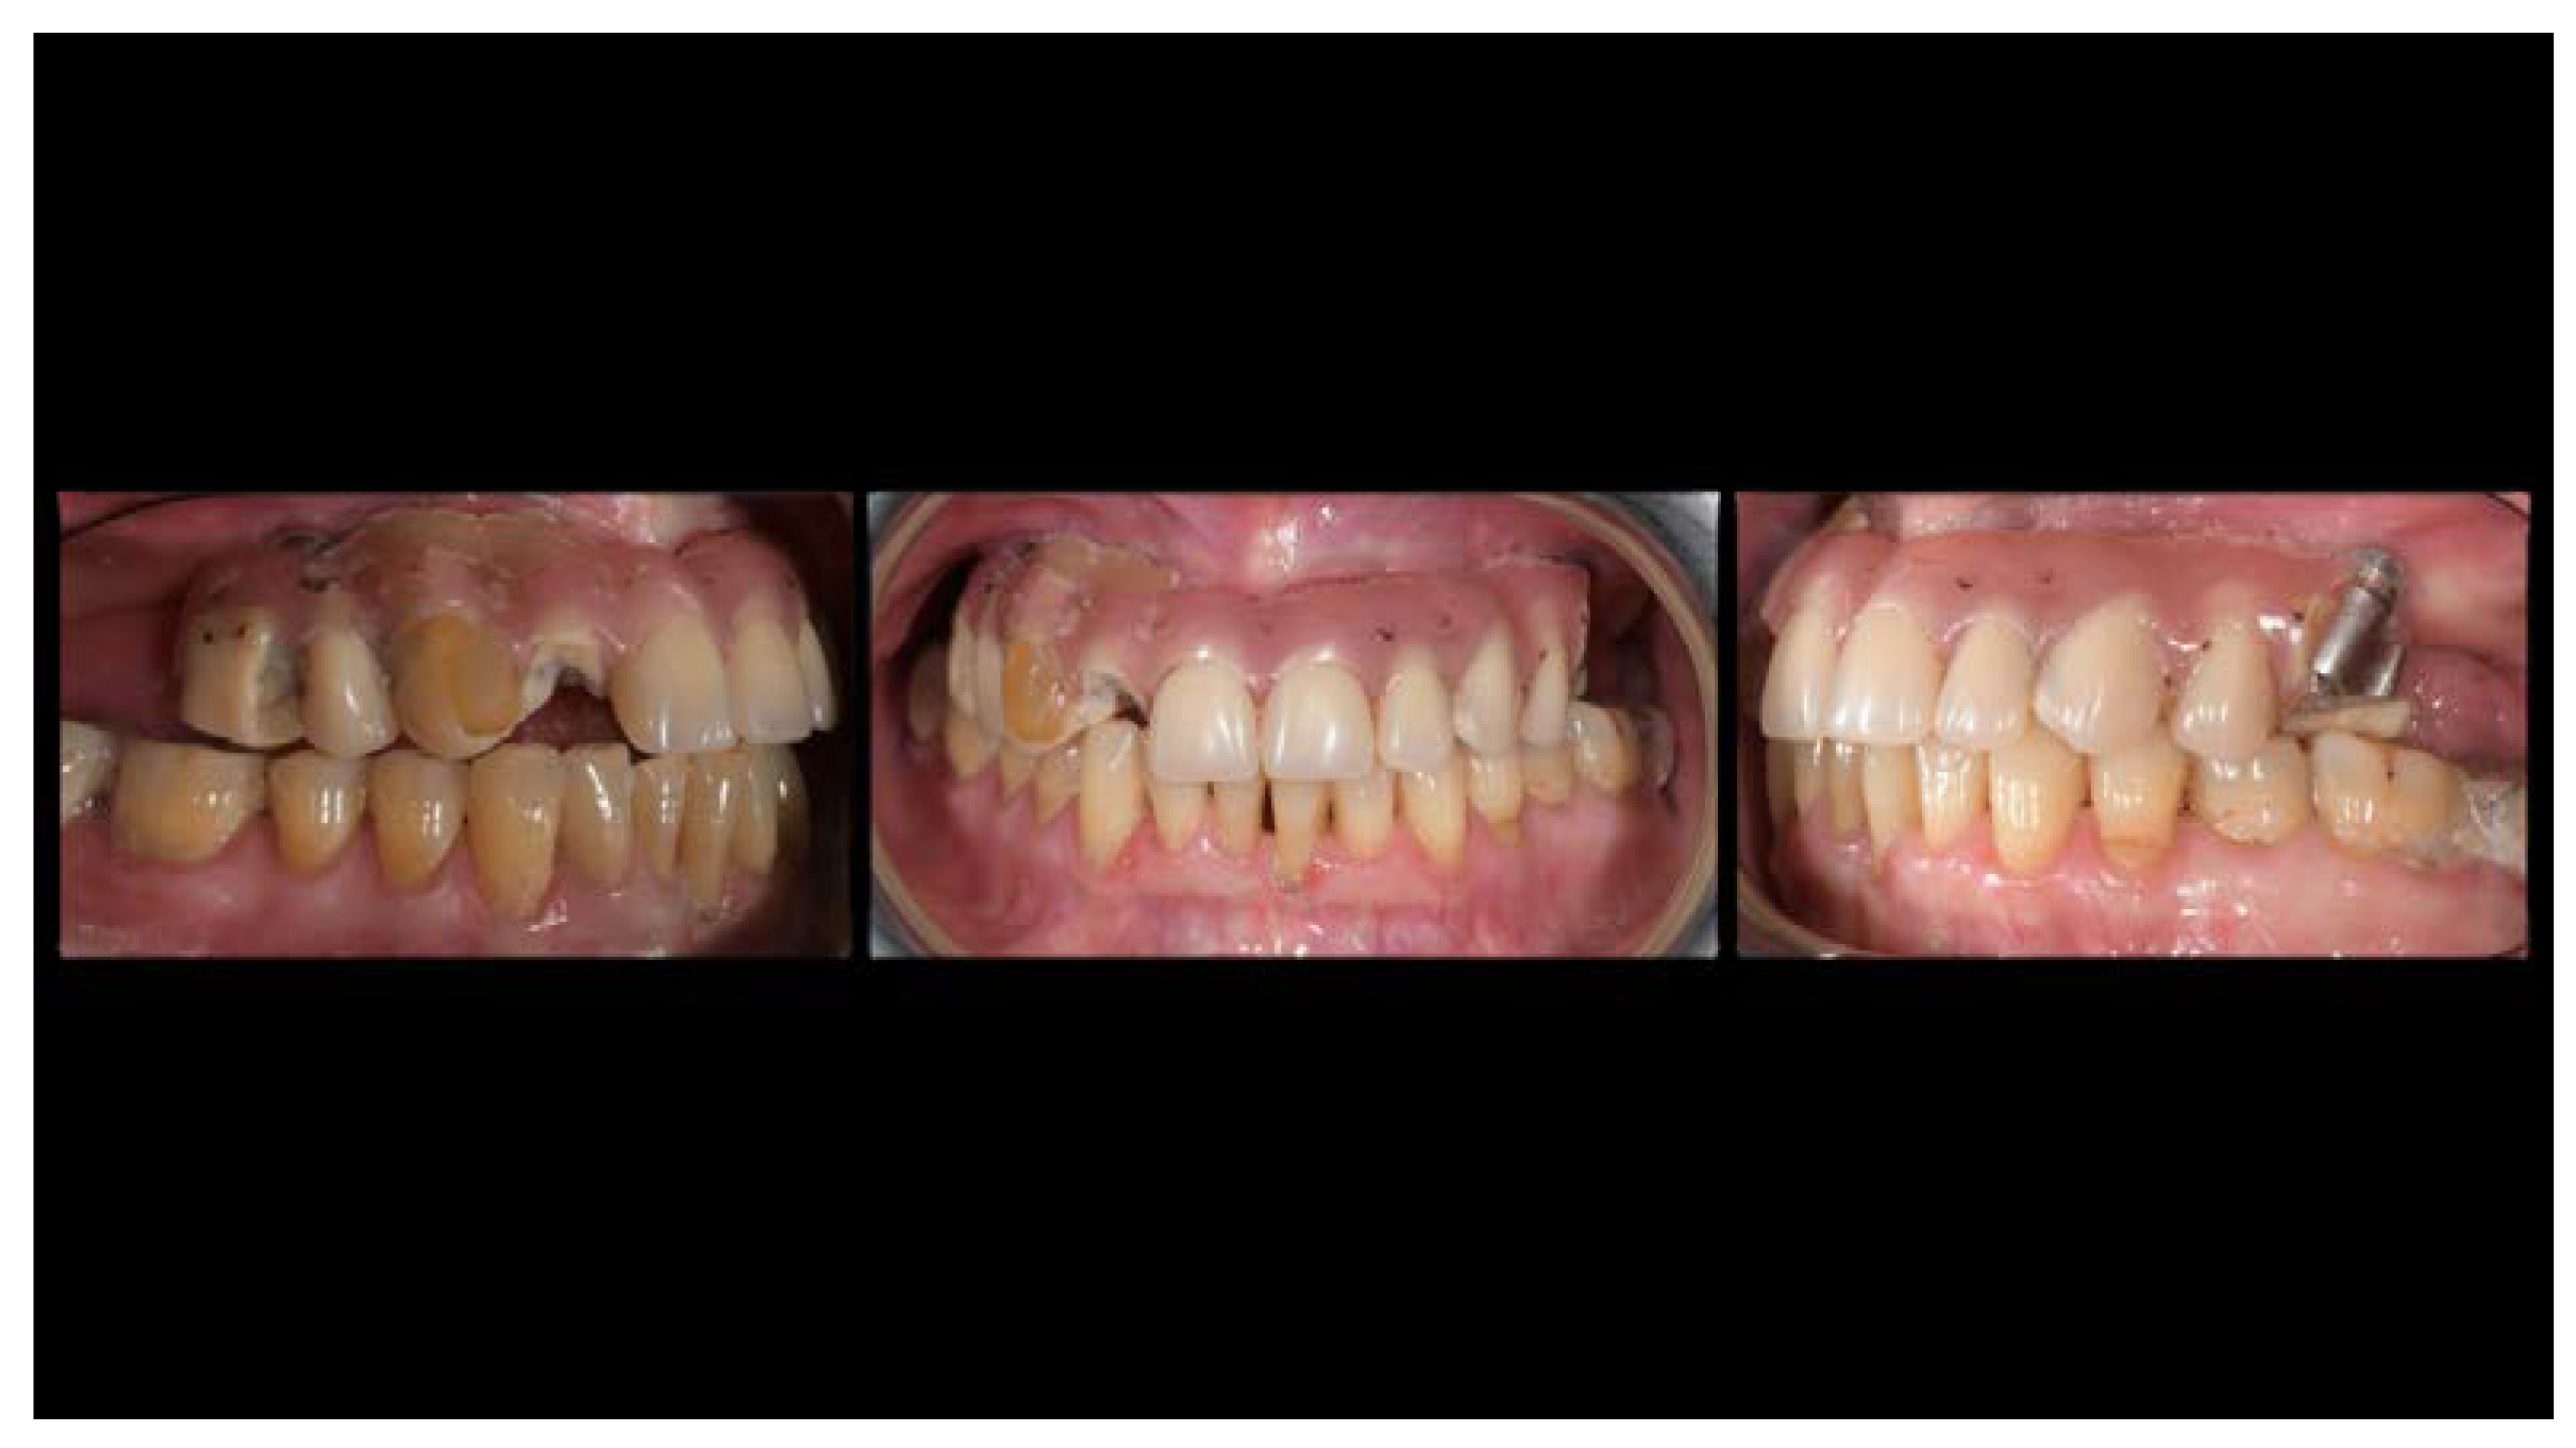

A partially edentulous 78-year-old woman with a complete screw-retained implant-support hybrid prosthesis (Figure 1) in the upper jaw and natural dentition in the lower jaw was referred to a private center in Rome, Italy, due to several continuous breakages of the prosthetic part of the implant-supported rehabilitation. After a preliminary interview, the patient stated that the implant treatment was finished two years before, but she had never been comfortable with this prosthesis (Figure 2). Relevant symptoms were phonetic difficulties, inability to maintain hygiene, and repeated breakages, leading to functional and esthetic issues (Figure 3). After that, the patient’s medical history was collected, and preoperative photographs, radiographs, periodontal screening results, and model casts were obtained for initial evaluation (Figure 4). During the clinical examination, the actual prosthesis was unscrewed, due to teeth detachments, and replaced with the old temporary prosthesis delivered by the patient. Both existing prostheses were evaluated and judged inaccurate, with particular attention to the fit of the prosthesis, the vertical dimension of occlusion, phonetics, facial support, and lip position. All the possible treatment options were then discussed and evaluated together with the patient. The main concerns of maintaining the previously placed implants were some exposed threads and the troubling disparallelism that makes the prosthetic treatment difficult, increasing the risk for biological complications and technical complications, respectively (Figure 5). Nevertheless, the patient refused a complete removable denture, so that implant removal would lead to placement of new implants, in combination with guided bone reconstruction and soft tissue management. This treatment plan may have the risks of implant failure and increased patient morbidity (Table 1 and Table 2). An implant-supported fixed dental prosthesis was initially excluded due to the implant’s disparallelism. Hence, a maxillary implant-supported overdenture was initially considered quite possibly the best therapeutic option.

Figure 3.

The internal part of the prosthetic restoration, the one in contact with the mucosa, shows the incorrect shape of the pink flange, which leads to the accumulation of plaque and food.